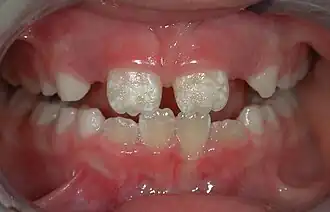

The normal color of enamel varies from light yellow to grayish (bluish) white. It has been suggested that the color is determined by differences in the translucency of enamel, yellowish teeth having a thin, translucent enamel through which the yellow color of the dentin is visible and grayish teeth having a more opaque enamel. The translucency may be attributable to variations in the degree of calcification and homogeneity of the enamel. At the edges of teeth where there is no dentin underlying the enamel, the color sometimes has a slightly blue or translucent off-white tone, easily observable on the upper incisors. Since enamel is semitranslucent, the color of dentin and any material underneath the enamel strongly affects the appearance of a tooth. The enamel on primary teeth has a more opaque crystalline form and thus appears whiter than on permanent teeth.